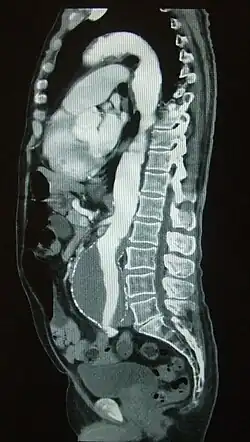

An abdominal aortic aneurysm is usually diagnosed by physical exam, abdominal ultrasound, or CT scan. Plain abdominal radiographs may show the outline of an aneurysm when its walls are calcified. However, the outline will be visible by X-ray in less than half of all aneurysms. Ultrasonography is used to screen for aneurysms and to determine their size if present. Additionally, free peritoneal fluid can be detected. It is non-invasive and sensitive, but the presence of bowel gas or obesity may limit its usefulness.[30] CT scan has nearly 100% sensitivity for an aneurysm and is also useful in preoperative planning, detailing the anatomy and possibility for endovascular repair. In the case of suspected rupture, it can also reliably detect retroperitoneal fluid. Alternative less often used methods for visualization of an aneurysm include MRI and angiography.[31]

An aneurysm ruptures if the mechanical stress (tension per area) exceeds the local wall strength; consequently, peak wall stress (PWS),[32] mean wall stress (MWS),[33] and peak wall rupture risk (PWRR)[34] are more reliable parameters than diameter to assess AAA rupture risk. Medical software allows computing these rupture risk indices from standard clinical CT data and provides a patient-specific AAA rupture risk diagnosis.[35][36][37] This type of biomechanical approach has been shown to accurately predict the location of AAA rupture.[36][37][38]